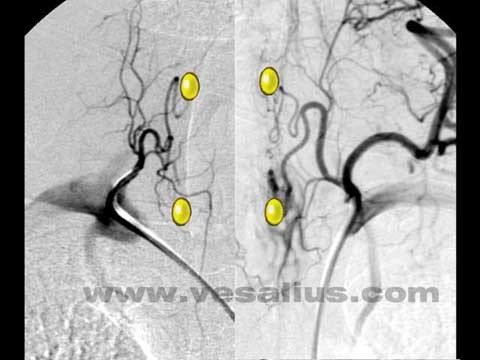

- Sestamibi ssintiqrafiya metodu 99mTc – izotopların (MİBİ) toxumada toplanma effektliyinə əsaslanır. MİBİ-nin anormal paratiroidlərin lokalizasiyasını aşkar etmə həssaslığı USM-dən daha yüksək olub 68-93%-dır.

- SPECT/KT (Single photon emission computed tomography) əsasən dərin, kiçik, ektopik və mediastinal lokalizasiyalı pataloji ocağı təyin etməyə imkan verir. Bu müayinənin həssaslığı 95%-dir.

- Qamma ötürücü – əməliyyat önü MİBİ ssintiqrafiya ilə paratiroid törəməsi müəyyən edilən xəstələrdə tətbiq olunur. Paratiroid vəzində tutulan sestamibidən yayılan qamma şüaların ötürücü vasitəsilə tutulması prinsipinə əsaslanır.

Görüntüləmə rəhbərliyi ilə icra edilən minimal invaziv paratiroidektomiya yeni bir cərrahi üsuldur. Əməliyyat öncə paratiroidi təyin etmək üçün radiometriya metodundan istifadə olunur. Bunun üçün əməliyyatdan 2 saat əvvəl vena daxilinə 18 mCİ 99mTc vurulur. Qamma prob yardımı ilə kəsik yeri müəyyənləşdirilir və adenomanın yeri təyin olunur. Bu üsul qalxanabənzər vəz olmadığı, təkrar əməliyyat və ya ektopik paratiroid adenomu olanlarda daha faydalı olur.